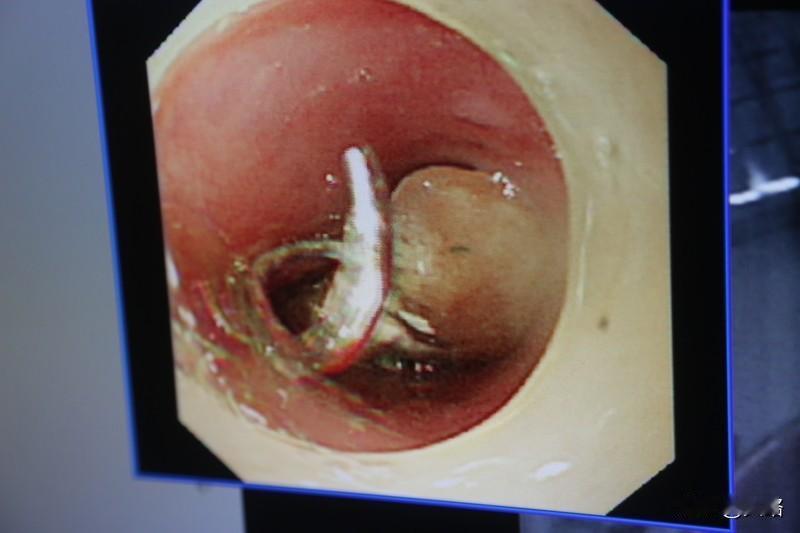

怀孕本是件幸福的事,但全球不足50例的罕见肝脏妊娠,却让准妈妈们面临巨大生命威胁。 福建30岁女子和40岁王女士都遭遇了这罕见情况。她们起初检查发现怀孕,子宫内却没胚胎,进一步检查才发现胎儿竟在肝脏上。肝脏高度血管化,受精卵在此发育,会侵蚀肝脏,引发破裂大出血,死亡风险远超普通宫外孕。 好在两位女士经及时手术转危为安。这提醒广大准妈妈,怀孕过程并非都顺风顺水,定期产检很重要,有异常症状要及时就医。

怀孕本是件幸福的事,但全球不足50例的罕见肝脏妊娠,却让准妈妈们面临巨大生命威胁。 福建30岁女子和40岁王女士都遭遇了这罕见情况。她们起初检查发现怀孕,子宫内却没胚胎,进一步检查才发现胎儿竟在肝脏上。肝脏高度血管化,受精卵在此发育,会侵蚀肝脏,引发破裂大出血,死亡风险远超普通宫外孕。 好在两位女士经及时手术转危为安。这提醒广大准妈妈,怀孕过程并非都顺风顺水,定期产检很重要,有异常症状要及时就医。